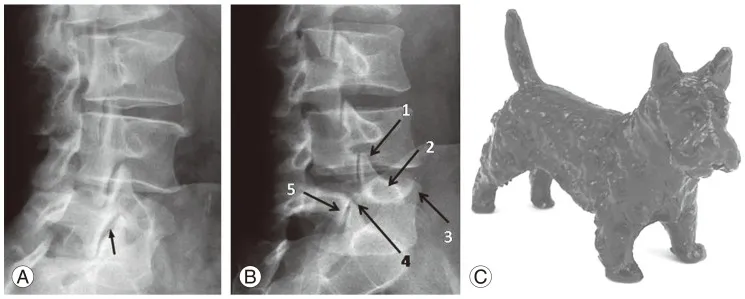

⭐ The 'Scottie dog' sign on oblique lumbar radiographs, where the 'collar' represents the pars interarticularis fracture, is characteristic of isthmic spondylolisthesis.

- Spondylolisthesis: Meyerding grading; "scotty dog" sign for pars defect.